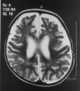

Infantile osteopetrosis